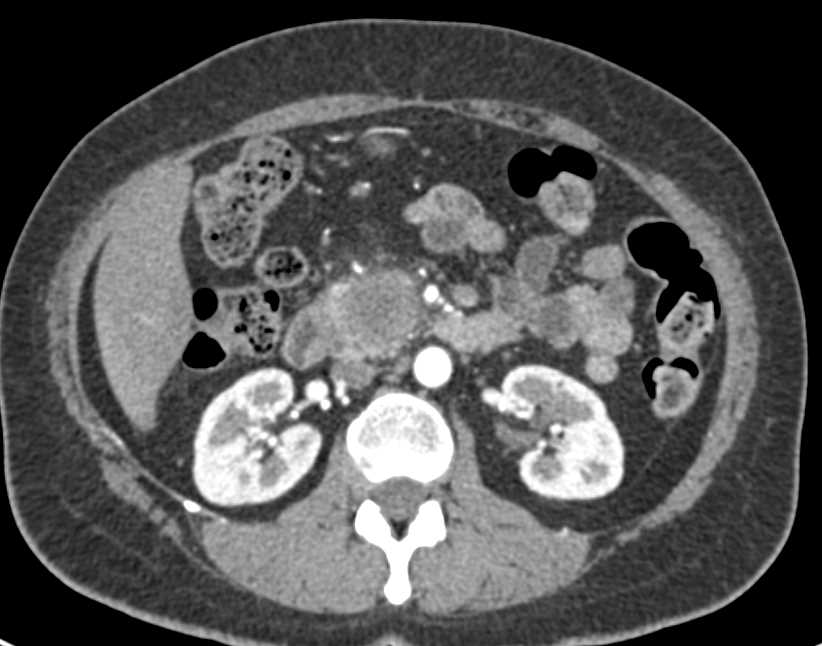

Adenocarcinoma of the Head of the Pancreas